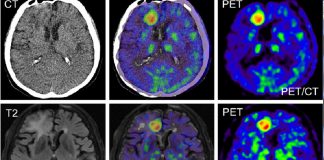

Özellikle son 20 yıldaki teknolojik gelişmelerden en çok elektronik ve bilgisayar alanındakiler tıpta yeni ufuklar açmıştır. Tüm görüntüleme yöntemlerinin temelini oluşturan bu alanlardaki gelişmeler...